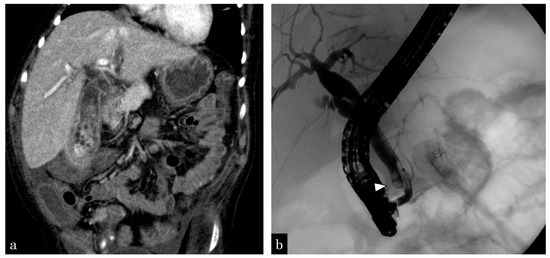

3.1.3. Patient 3

3.1.4. Patient 4